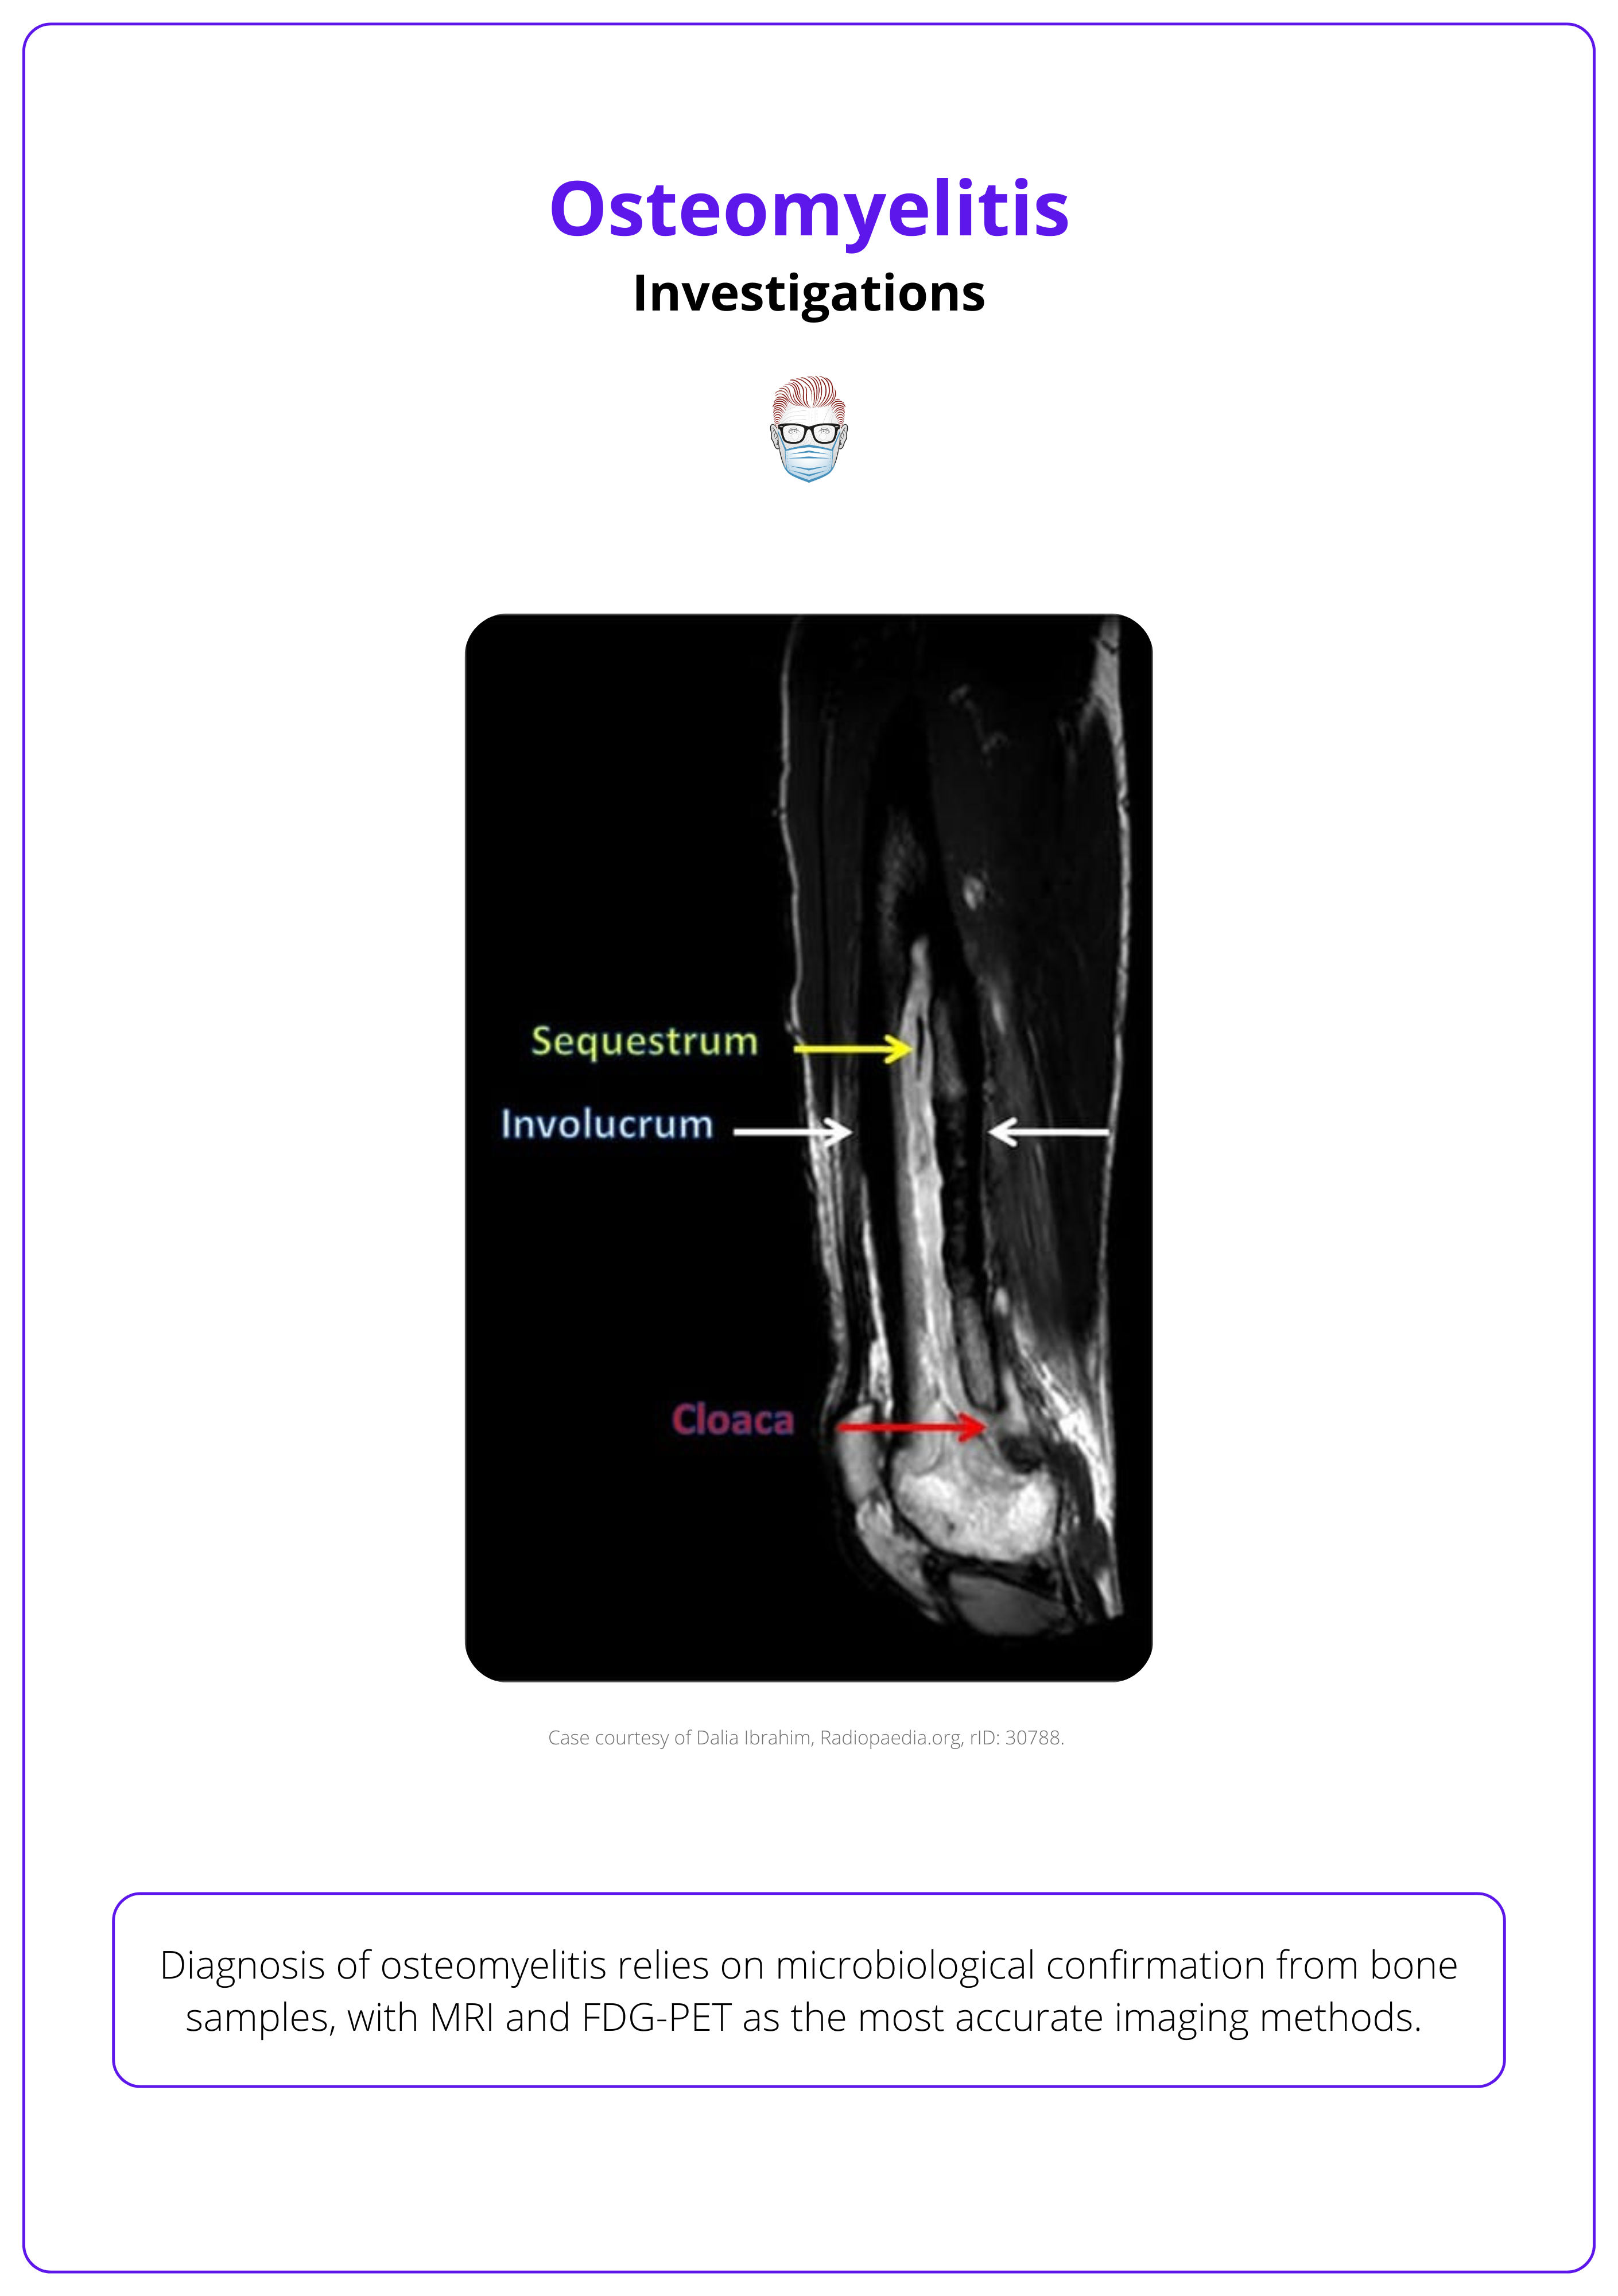

Diagnosis of osteomyelitis relies on microbiological confirmation from bone samples, with MRI and FDG-PET as the most accurate imaging methods. Antibiotics should be withheld until samples are obtained to avoid masking the infection.

Radiological Investigations

Imaging is crucial for identifying the extent of bone and soft tissue involvement, with MRI and FDG-PET offering the highest sensitivity and specificity.

Plain X-ray Detects bone changes only after significant mineral loss (≥40%) and infection spread (≥1 cm). Findings include:

- Periosteal Reaction: Formation of Codman’s triangle due to rapid periosteal elevation.

- Endosteal Scalloping and Osteopenia: Indicators of chronic bone involvement.

- Sequestrum and involucrum